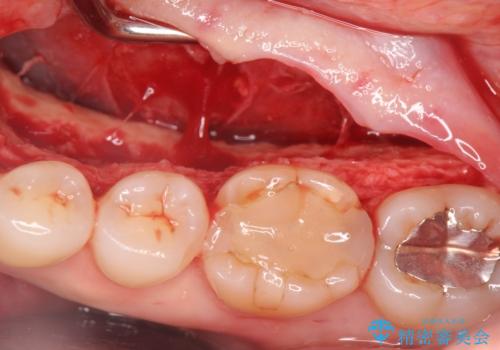

話すのに邪魔な、下顎骨隆起の切除

- 矯正治療を開始するのに伴い、滑舌を含めた改善を計るために、発音の邪魔となる下顎骨隆起の切除を計画します。

手術時間は約30分程度(大きさにより)今回は手術中に、静脈麻酔を行うことで負担なく治療を行う計画としました。

長年気になっていた骨隆起が短時間でなくなり、満足いただくことができました。